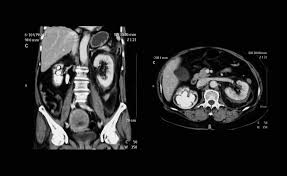

CT Scan Abdomen: 5 Hal Penting yang Perlu Anda Ketahui Sebelum Pemeriksaan

ct scan abdomen

Pemeriksaan CT scan abdomen (computed tomography scan) adalah prosedur pencitraan diagnostik yang sering direkomendasikan dokter untuk mendapatkan gambaran rinci dan akurat dari organ, pembuluh darah, dan struktur tulang di dalam perut. Dengan kemampuannya menghasilkan gambar 3D berlapis, CT scan abdomen menjadi alat penting dalam mendiagnosis dan memantau berbagai kondisi medis. Agar Anda lebih siap, berikut … Read more